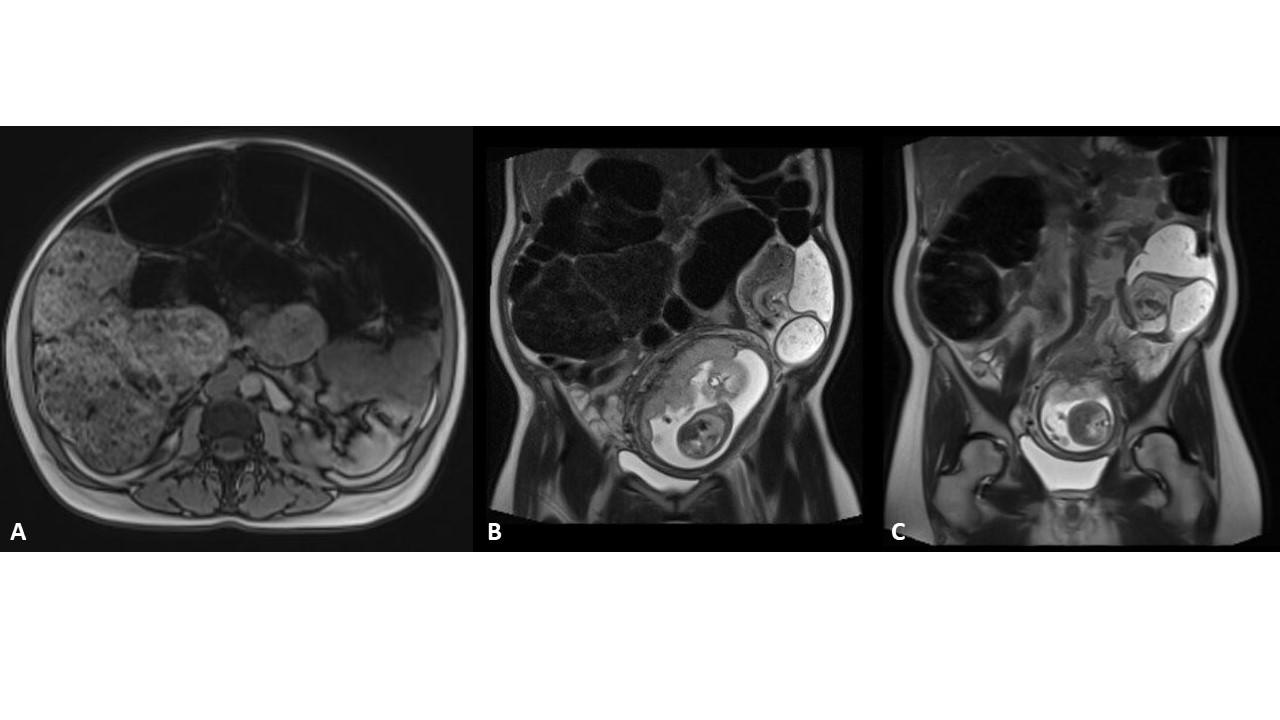

A 40-year-old pregnant woman presented with acute constipation and abdominal distention. A sigmoid volvulus was diagnosed (Figure 1). There was a transition point in the sigmoid colon with a “mesenteric swirl sign” (Figures 1B, 1C).